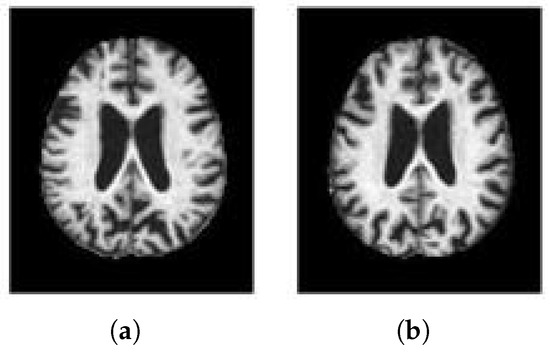

It can be seen from the experimental results that the five metrics have been improved compared with WSDAN, and the accuracy is as high as 99.61%, which indicates that WS-AMN model can almost correctly classify AD and NC. It shows that this method has good classification accuracy. Figure 9 shows the visualization results of WSDAN and WS-AMN. We can see that the feature extraction range of the improved network is larger, more refined, and contains more effective information.

The early and accurate diagnosis of Alzheimer’s disease is very important for disease prevention. In this paper, we propose WS-AMN that fuses weak supervision and attention mechanism. CNN is the most successful deep model in image analysis, which provides help for image-aided classification. As the depth of CNN continues to deepen, a series of problems follow, such as gradient disappearance, gradient explosion and so on. The emergence of ResNet alleviates these problems, the residual block solves the problem of network degradation, and the skip connection makes the network deeper, showing excellent performance. In this article, we compare the classification accuracy of different CNN networks. Compared with VGG16, VGG19, Inception_V3 and ResNet101, ResNet50 has the highest accuracy rate of 92.58%. We introduce attention mechanism into the residual block of the backbone network, so that the network not only focuses on the key feature areas to improve the classification accuracy, but also generates an attention map to guide attention cropping and attention dropping. Enter the network together for training to enhance the data. Then the feature map generated by the backbone network and the attention map are fused through BAP. It is obvious from the heat map in Figure 9 that our WS-AMN is able to extract more and more accurate effective features.

Figure 9. Visual comparison (a) Input image. (b) WSDAN. (c) WS-AMN.